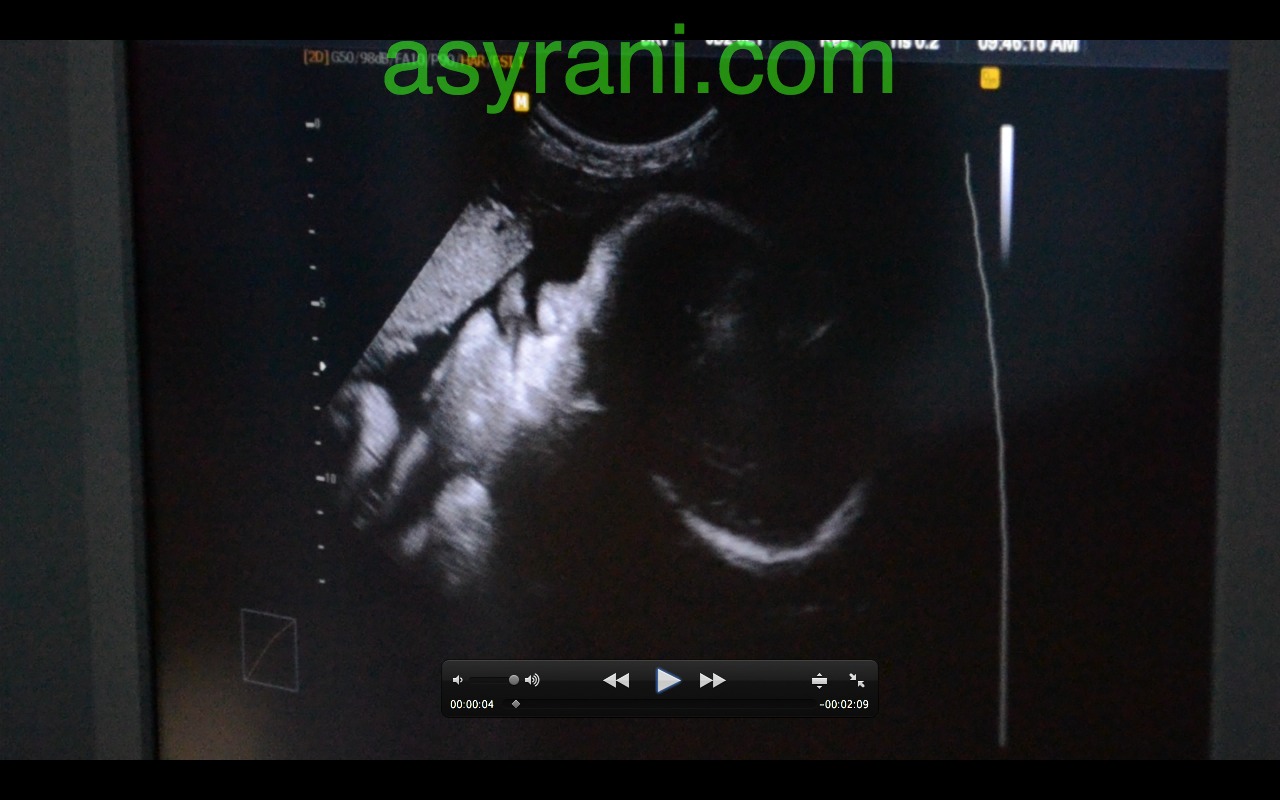

Pandangan sisi muka baby nampak hidung, diatasnya adalah uri (placenta)

Muka baby dalam bentuk 3D. Kelihatan hidung, mata dan bibir atas. Yang lain tertutup oleh uri dan bayang-bayang uri

Gambar 3D scan yang jelas sedikit. Kelihatan tangannya menutup mata